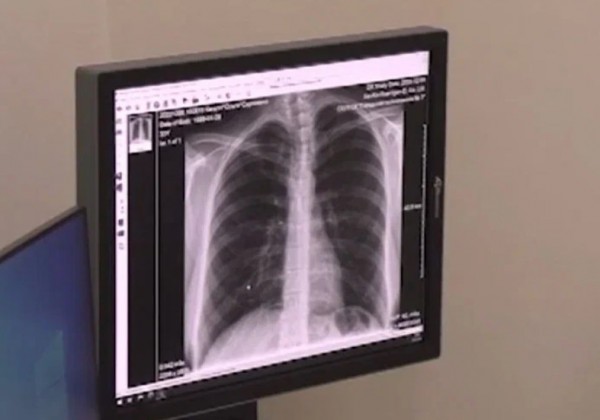

Недобросовестный поставщик лишил Пятигорский медцентр проводить рентгенографию

Общество с ограниченной ответственностью «Цифровая симфония» попало в реестр недобросовестных поставщиков на 2 года.